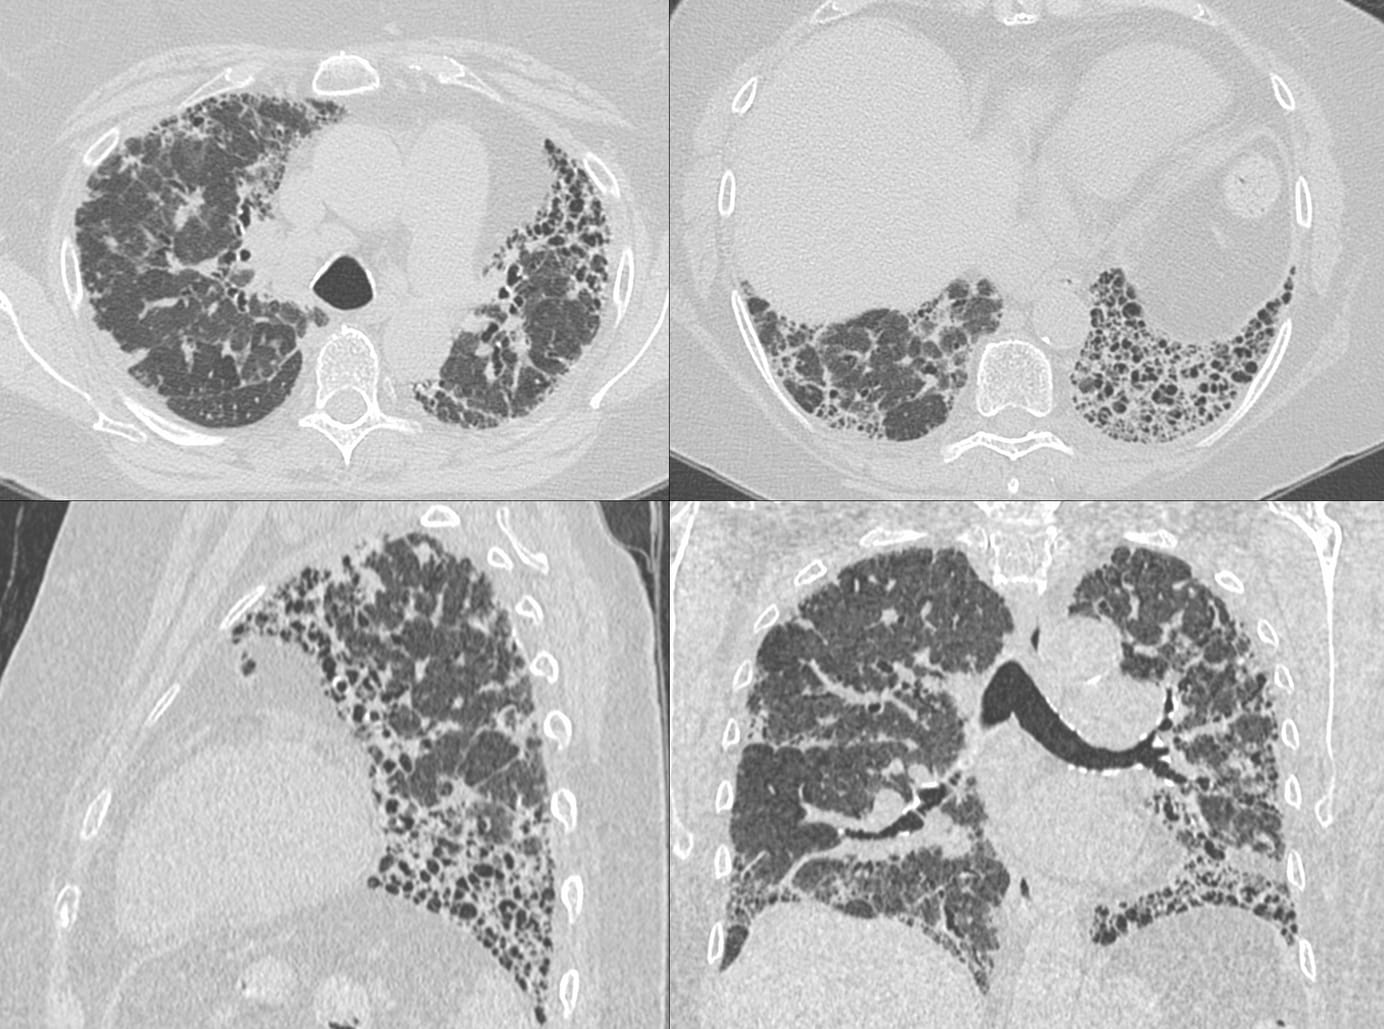

A 10 years story of progressive pulmonary fibrosis in a patient with chronic fibrotic hypersensitivity pneumonitis

Case 58: Progressive Pulmonary Fibrosis - Scleroderma ILD Members Public

Scleroderma ILD, secondary PPFE and progressive pulmonary fibrosis (PPF)